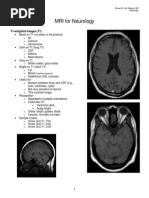

2. T1 and T2-weighted

a. Two fundamental anatomic sequences

b. T1 TR short and TE short (repetition time, echo time)

c. T2 TR long and TE long

d. Best way to differentiate is the relationship between gray matter

and white matter

i. T1 gray matter is gray (hypointense) and white matter is

white (hyperintense)

1. Hyperintense on T1: blood product, fat, proteinaceous

material and contrast enhancement

ii. T2 gray matter is white and white matter is gray